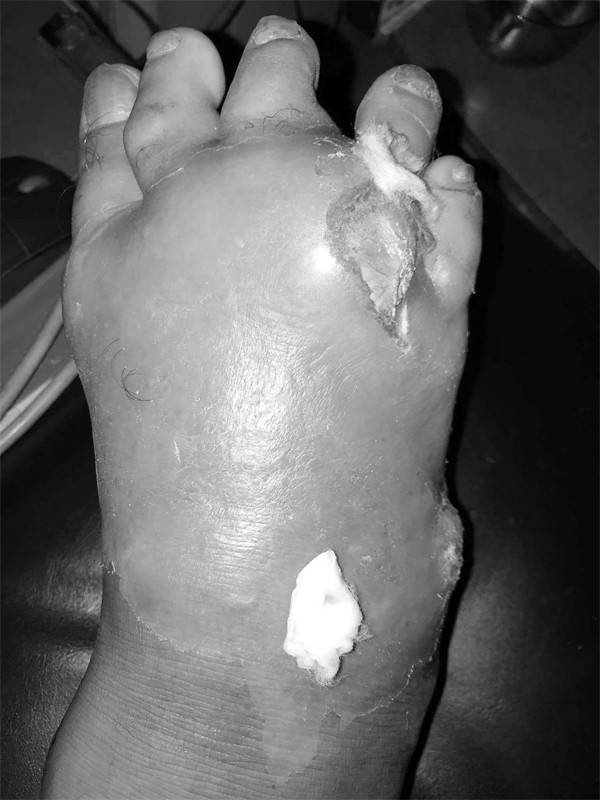

Hình ảnh bàn chân của bệnh nhân vào khám với tổn thương do gout. Ảnh: BSCC.

Các triệu chứng xuất hiện đột ngột ban đêm, bệnh nhân thức dậy vì đau khớp, thường là khớp bàn - ngón chân cái (60-70%): Khớp sưng to, đỏ, phù nề, căng bóng, nóng, đau dữ dội và ngày càng tăng, va chạm nhẹ cũng rất đau. Lúc đầu, bệnh nhân chỉ viêm một khớp sau đó có thể viêm nhiều khớp. Ngoài khớp ra, túi thanh dịch, gân, bao khớp cũng có thể bị thương tổn.